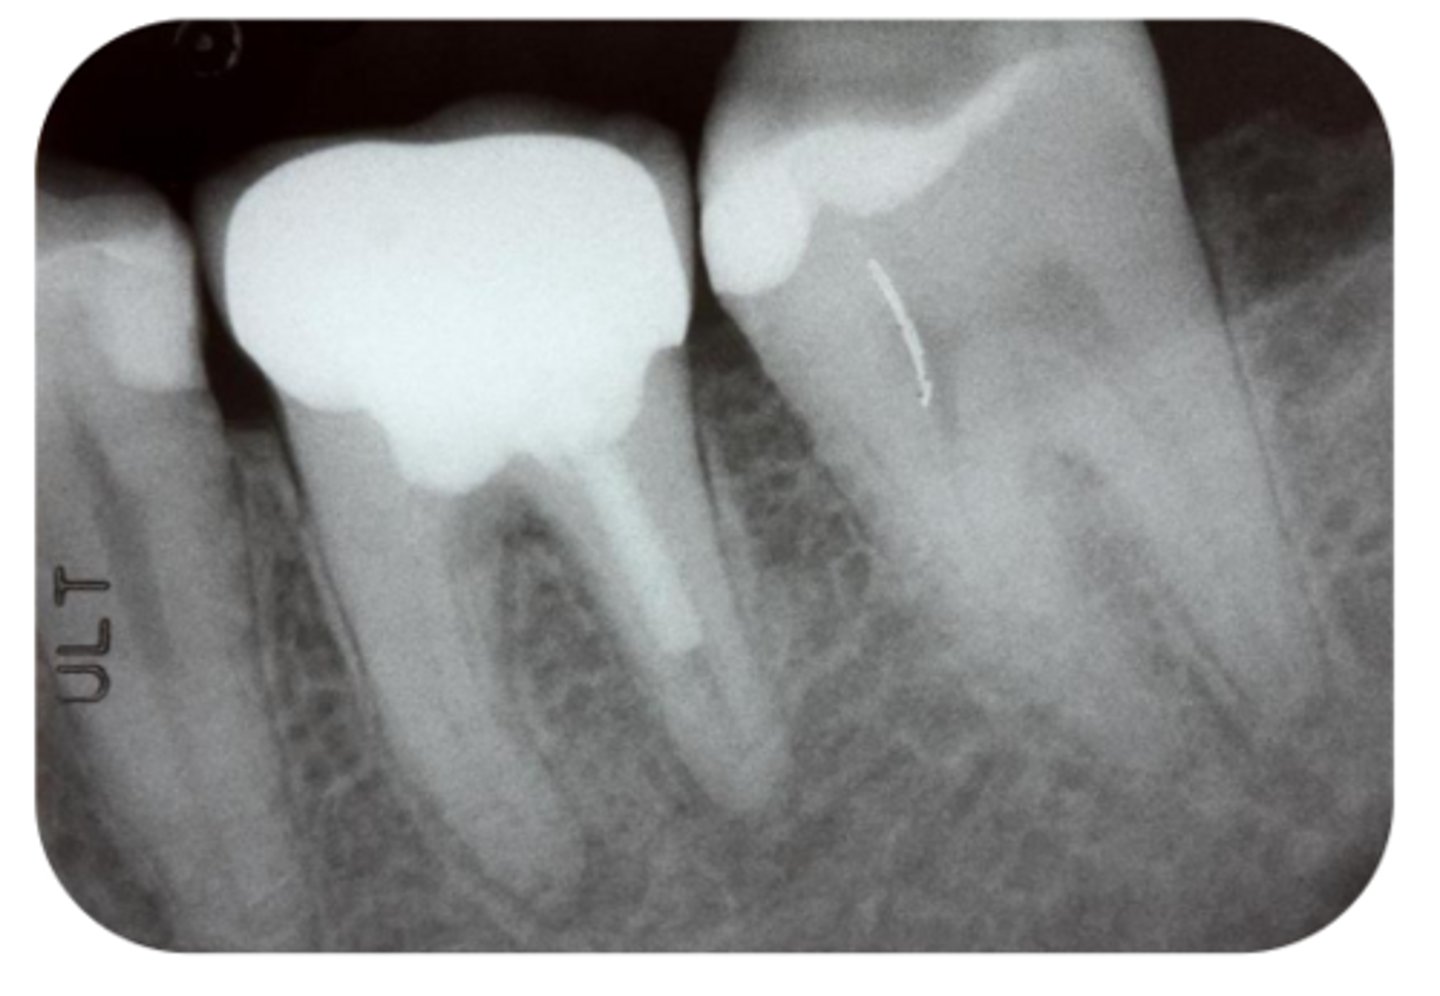

What are the radiographic findings on #19?

- Crown

- Post D Canal

- PARL Mesial and Distal Root

- PARL in Mesial and Distal Root

- Discontinuation of LD